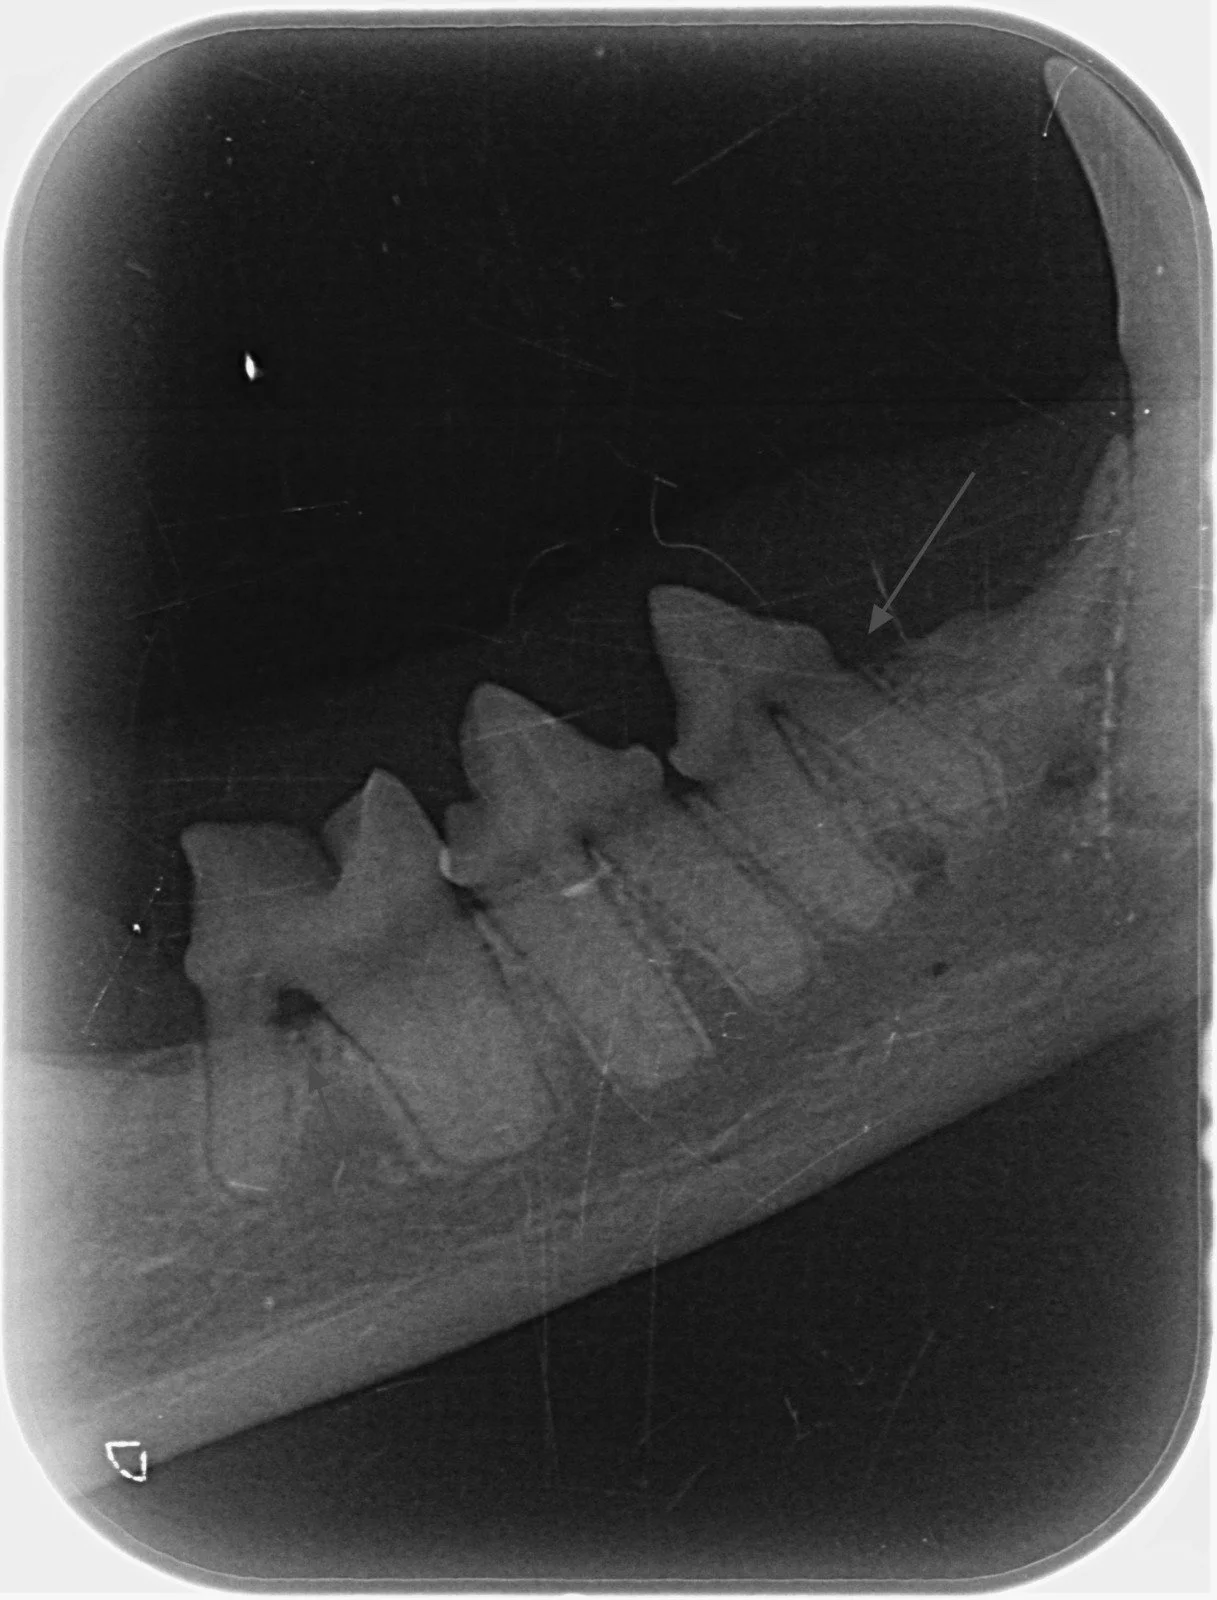

Radiografia intraorală la animalele de companie: diagnostic precis pentru sănătatea dentară

Problemele dentare sunt printre cele mai frecvente afecțiuni întâlnite la câini și pisici, însă multe dintre ele rămân ascunse sub gingie și nu pot fi observate la o simplă examinare vizuală. Radiografia intraorală veterinară este una dintre cele mai importante metode de diagnostic în stomatologia veterinară modernă, deoarece permite evaluarea detaliată a dinților, rădăcinilor și osului alveolar.

Radiografia intraorală este o tehnică imagistică specializată prin care se obțin imagini detaliate ale dinților și structurilor din jurul acestora, folosind plăcuțe fosforice plasate direct în cavitatea orală a pacientului.

Spre deosebire de radiografia clasică a craniului, radiografia intraorală oferă imagini mult mai precise și focalizate, fiind esențială în evaluarea sănătății dentare la câini și pisici.

De multe ori, peste 60% din structura dintelui se află sub gingie, ceea ce face imposibilă diagnosticarea corectă fără imagistică dentară.